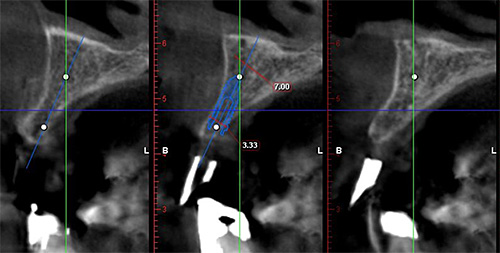

赤丸の部位のCT検査像です。骨が先細りしているのがわかります。

CTデータをもとに、インプラントの埋入をシミュレーションし、精密な計画を立てます。前歯のインプラントで難しいのは、埋入位置が0,5mmと狂うと取り返しがつきません。

術後のCT画像が重要です。シュミレーションとほとんど同じ位置に埋入できました。